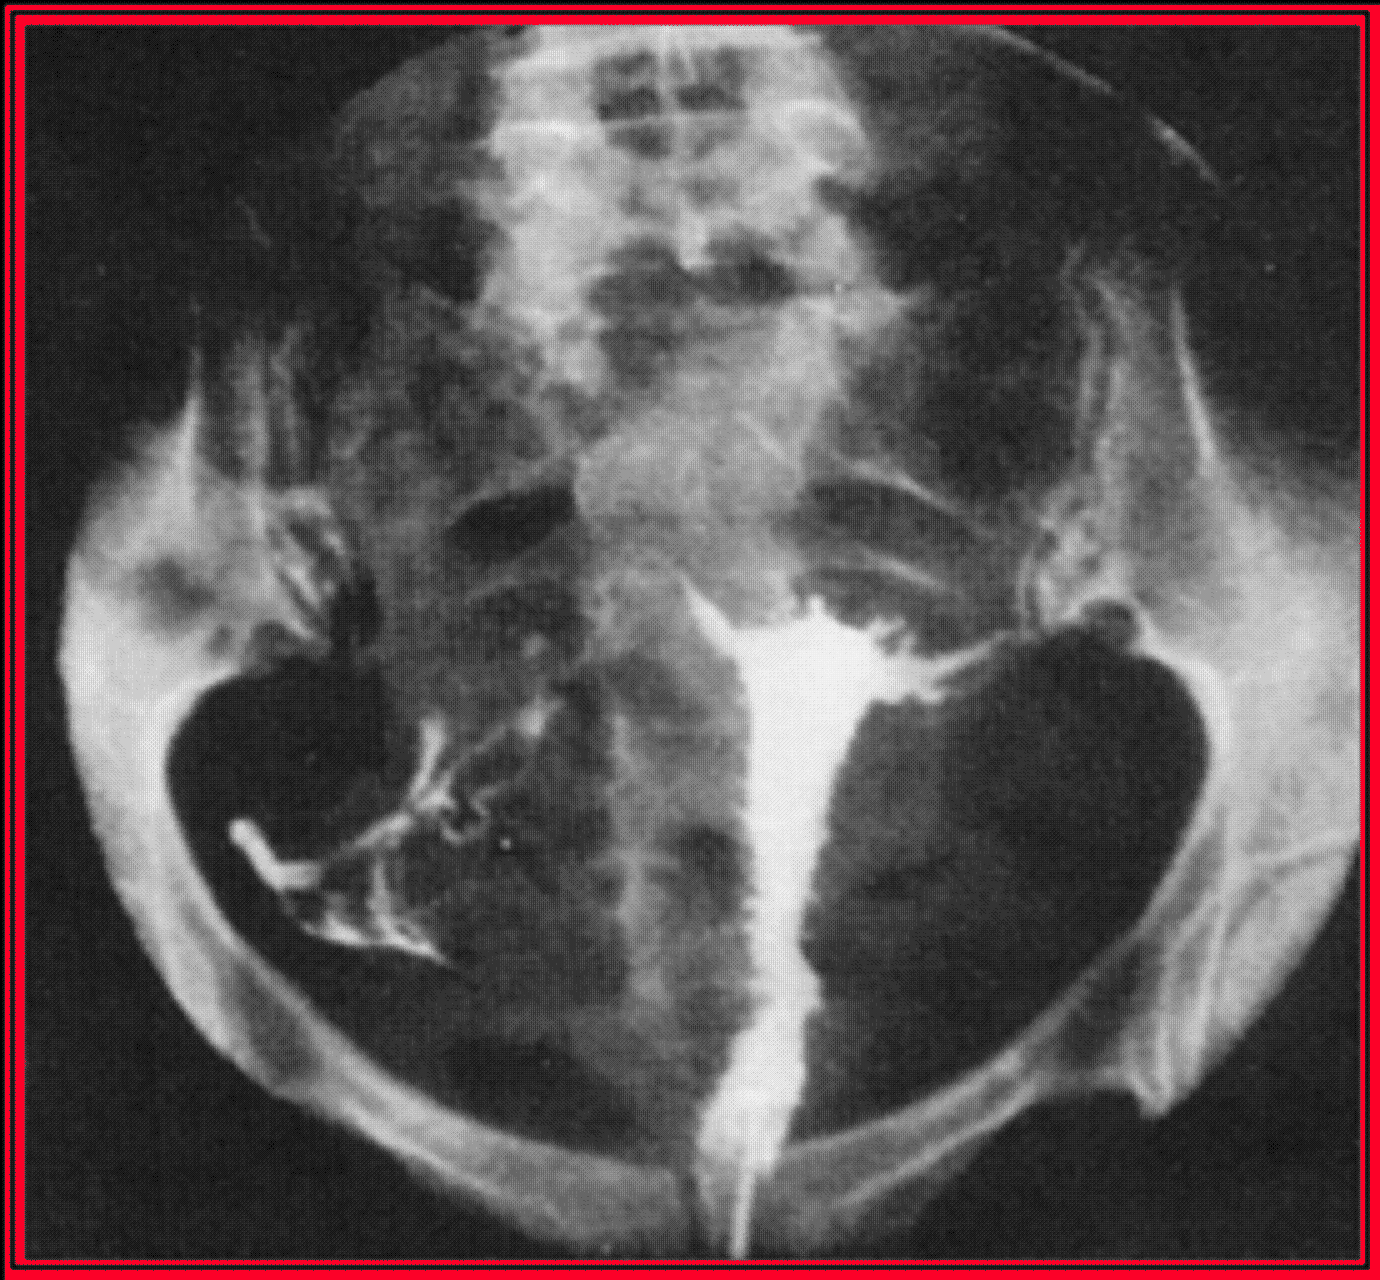

Il existe deux techniques de préhension du sol, soit l'appareillage traditionnel à l'aide d'une canule de Riazzi-Palmer, soit la ventouse cervicale à embout de Bommelaer, qui est moins douloureuse. Après la saisie du col, il faut enlever le spéculum, pour permettre une bonne vision du col et de l'endocol. Le début de l'examen commence par la prise d'un cliché sans préparation. L'opérateur doit exercer une forte traction sur le col pour redresser l'utérus, on injecte lentement 0,5 ml de liquide de contraste et le premier cliché est pris, c'est le cliché de remplissage précoce qui permet de voir la cavité corporéale. Ensuite, après injection lente de 2 à 3 ml, on réalise le cliché de remplissage complet qui renseigne sur la cavité, l'isthme et le fuseau endocervical, le contrôle téléradioscopique permet de vérifier le début du remplissage tubaire. La troisième étape est le cliché de profil, la patiente est placée en décubitus latéral, jambes repliées l'une sur l'autre, il faut lâcher momentanément la traction sur le col pour permettre à l'utérus de retrouver sa position naturelle. Ce cliché de profil renseigne sur la position de l'utérus, sur l'état de l'isthme et du col et sur la position des trompes. On reprend ensuite la traction sur le col et on injecte 1 à 2 ml pour réaliser le cliché d'évacuation sur lequel outre la cavité, les trompes seront analysées. La dernière étape est le cliché tardif, 15 à 20 minutes après, qui permet d'apprécier la perméabilité tubaire, la sténoseDéfinitionModification anatomique qui se traduit par un rétrécissement d'une structure (canal, vaisseau). ou la perméabilité des pavillons, d'éventuelles adhérences péritonéales, la forme le volume des fossettes ovariennes.

De face en réplétion complète et après traction sur le col, de manière à placer la cavité utérine dans le prolongement du col, elle à la forme d'un triangle isocèle à base supérieure. Sa capacité oscille entre 3 et 10 ml environ. La longueur du fond et des bords est en moyenne de 3 à 4 cm. Le fond et les bords utérins sont rectilignes. Dans certains cas, il est possible au cours du cliché de remplissage de mettre en évidence, dans la région sus-isthmique, des images linéaires parallèles aux bords qui correspondent à des plis muqueux. De profil, la cavité utérine est fusiformeDéfinitionQui a la forme d'un fuseau, c'est-à-dire qui a ses deux extrémités se terminant en pointe.. Lorsque l'utérus est antéversé, elle forme avec le canal cervical un angle de 120° environ. Lorsque l'utérus est en position intermédiaire, le fond utérin se projette en direction de l'ombilic. En cas de rétroversion utérine, il se projette en regard du promontoire (rétroversion du premier degré), de la première pièce sacrée (deuxième degré) ou de l'articulation sacro-iliaque (troisième degré).

Après diffusion le long des franges du pavillon, le produit cerne assez fréquemment la surface externe des ovaires, réalisant l'image des fossettes ovariennesDéfinitionFossette ovarienne : Zone située latéralement dans le pelvis, limitée en avant par l'artère ombilicale, en arrière par l'uretère et l'artère iliaque interne et en haut par la veine iliaque externe.. On peut ainsi indirectement apprécier le volume des ovaires (normalement 3,5 cm de long sur 2 cm de large).

Le passage péritonéal

Affirmé parfois dès les premiers clichés, il s'apprécie en fait sur le cliché tardif. Il se traduit par un aspect marécageux occupant le petit bassinDéfinitionPetit bassin ou pelvis minor : Cadre osseux, sensiblement hémisphérique, de la forme et de la taille d'un petit bol, situé à la base du bassin, sous la cavité abdominale. et qui est obtenu par le brassage du produit provoqué par la mobilité des anses intestinales.